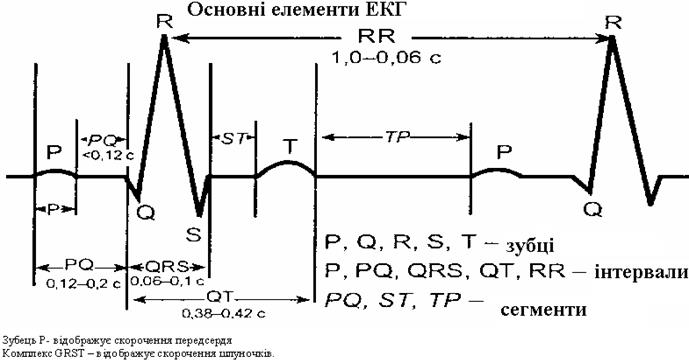

Фази серцевого циклу

Фази серцевого циклу